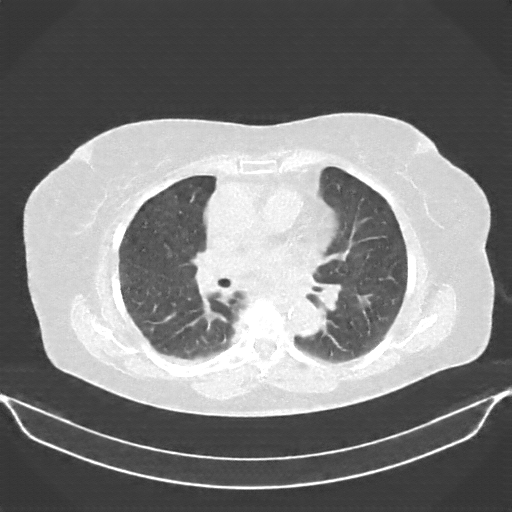

Targeted Slice 70 - Lung Window Analysis (Generated vs Real Venous)

0.676

Lung SSIM

119.5

Lung RMSE

52.1

Lung MAE

Average Lung Window Metrics Across All Slices (58 slices) - Generated vs Real Venous

0.690

Lung SSIM (Avg)

110.0

Lung RMSE (Avg)

49.3

Lung MAE (Avg)

Original NATIVE CT scan (input)

No window - Raw intensity values

Lung window (WL -600, WW 1500 β†’ Low βˆ’1350, High +150)